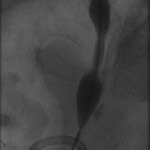

The above images belong to a middle-aged woman with cervical cancer, who developed impaired renal function when the cancer invaded and obstructed her distal ureters. Efforts by urologists to stent her ureters from below through her urethra failed, because the ureteral orifices were invisible. She was referred to the interventional radiology service for ante-grade intervention through the kidneys. Because she was prone on the table for the procedure, there is seeming reversal of her right and left sides.

Access was gained from the back into a dilated posterior calyx of each kidney and secured with a sheath. Antegrade pyelogram on each side revealed marked ureteral and calyceal dilation due to complete obstruction of the distal ureter. A wire was advanced into the urinary bladder past the obstruction, which was dilated with a non-compliant balloon when it resisted the deployment of a nephroureteral stent. The stent was successfully deployed after the balloon dilation.

If obstructions are easy to cross, internal ureteral stents may be placed across them, with one end of the stent in the renal pelvis and the other in the urinary bladder. The stents should be changed periodically through the urethra by urologists or interventional radiologists. Sometimes, as in the patient whose images are displayed above, the obstruction must be predilated to permit insertion of the ureteral stents. Alternatively, a drainage catheter called a nephrostomy catheter can be deployed into the renal pelvis to drain urine into a bag attached to it without crossing the obstruction.